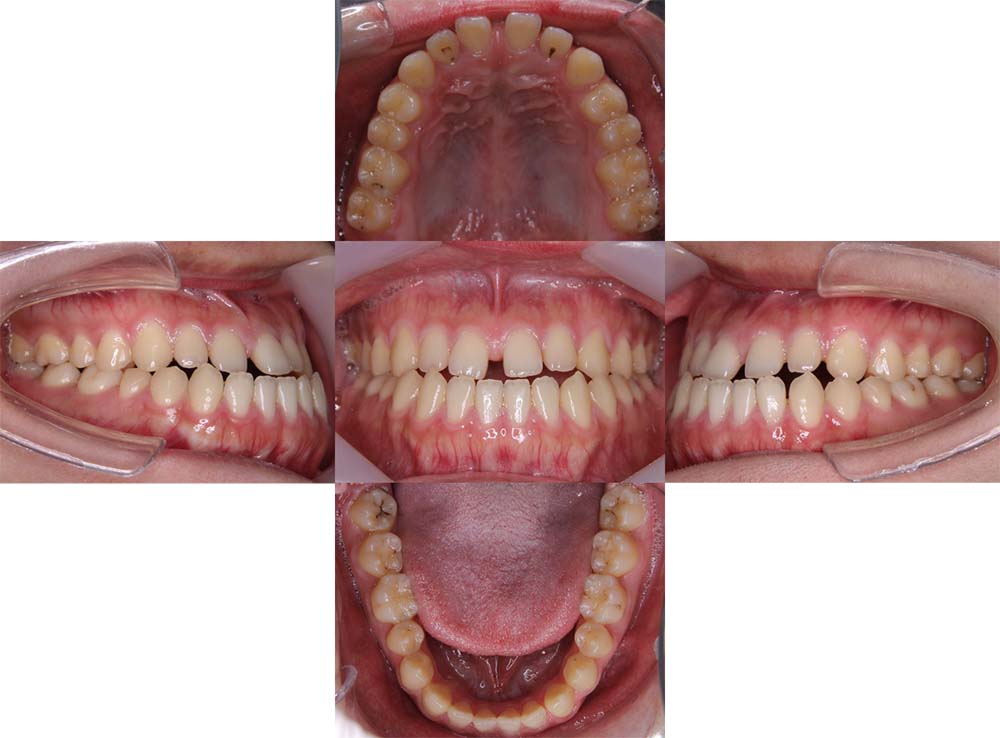

症例01

| 主訴 | 歯並びがガタガタしている。 |

| 診断名あるいは主な症状 | 叢生 |

| 年齢/性別 | 22歳・男性 |

| 矯正ステージ | 大人の矯正治療 |

| 治療方法 | ワイヤー矯正 |

| 抜歯部位/抜歯有無 | 非抜歯 |

| 治療内容 | 上顎大臼歯の遠心移動により前歯のガタガタを排列スペースを獲得し全顎的な排列を行った。 |

| 費用 | 85万円程度(2025.10時点の料金となります。) ※矯正基本料金、審美ブラケットを含む |

| 治療期間 | 2年4ヶ月 |

| 主なリスク・副作用 | 痛み、歯根吸収、歯肉退縮、虫歯、後戻り |